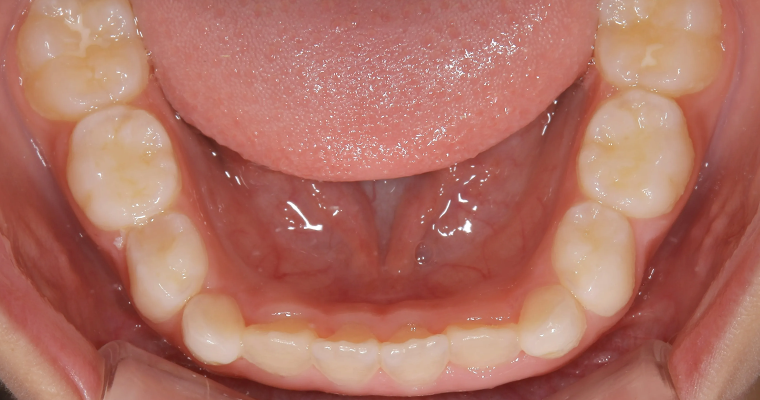

下顎咬合面観

BEFORE

AFTER

| 主訴 | 歯並びが悪い 乳歯と永久歯が重なっている 歯がまっすぐはえてこない |

|---|---|

| 治療期間 | 6-7ヶ月 |

| 治療費 | 440,000円(税込) ※調整、器具、治療後にお渡しするEFLine(矯正後の後戻りを防ぐ器具)も全て込みでの金額となっております。 |

| 治療内容 | 拡大床矯正 EF Lineで筋機能療法 |